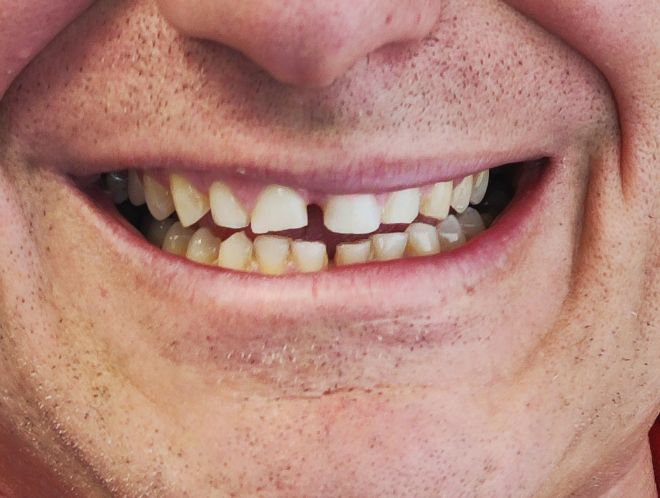

No es magia. Es planificación digital, coronas de cerámica de primera calidad y el Método Gnadent. El paciente de estas fotos recuperó su sonrisa — y la libertad de mostrarla.

Casos Antes y Después

Pacientes reales, resultados reales. Desliza para explorar.

← Arrastra para explorar →